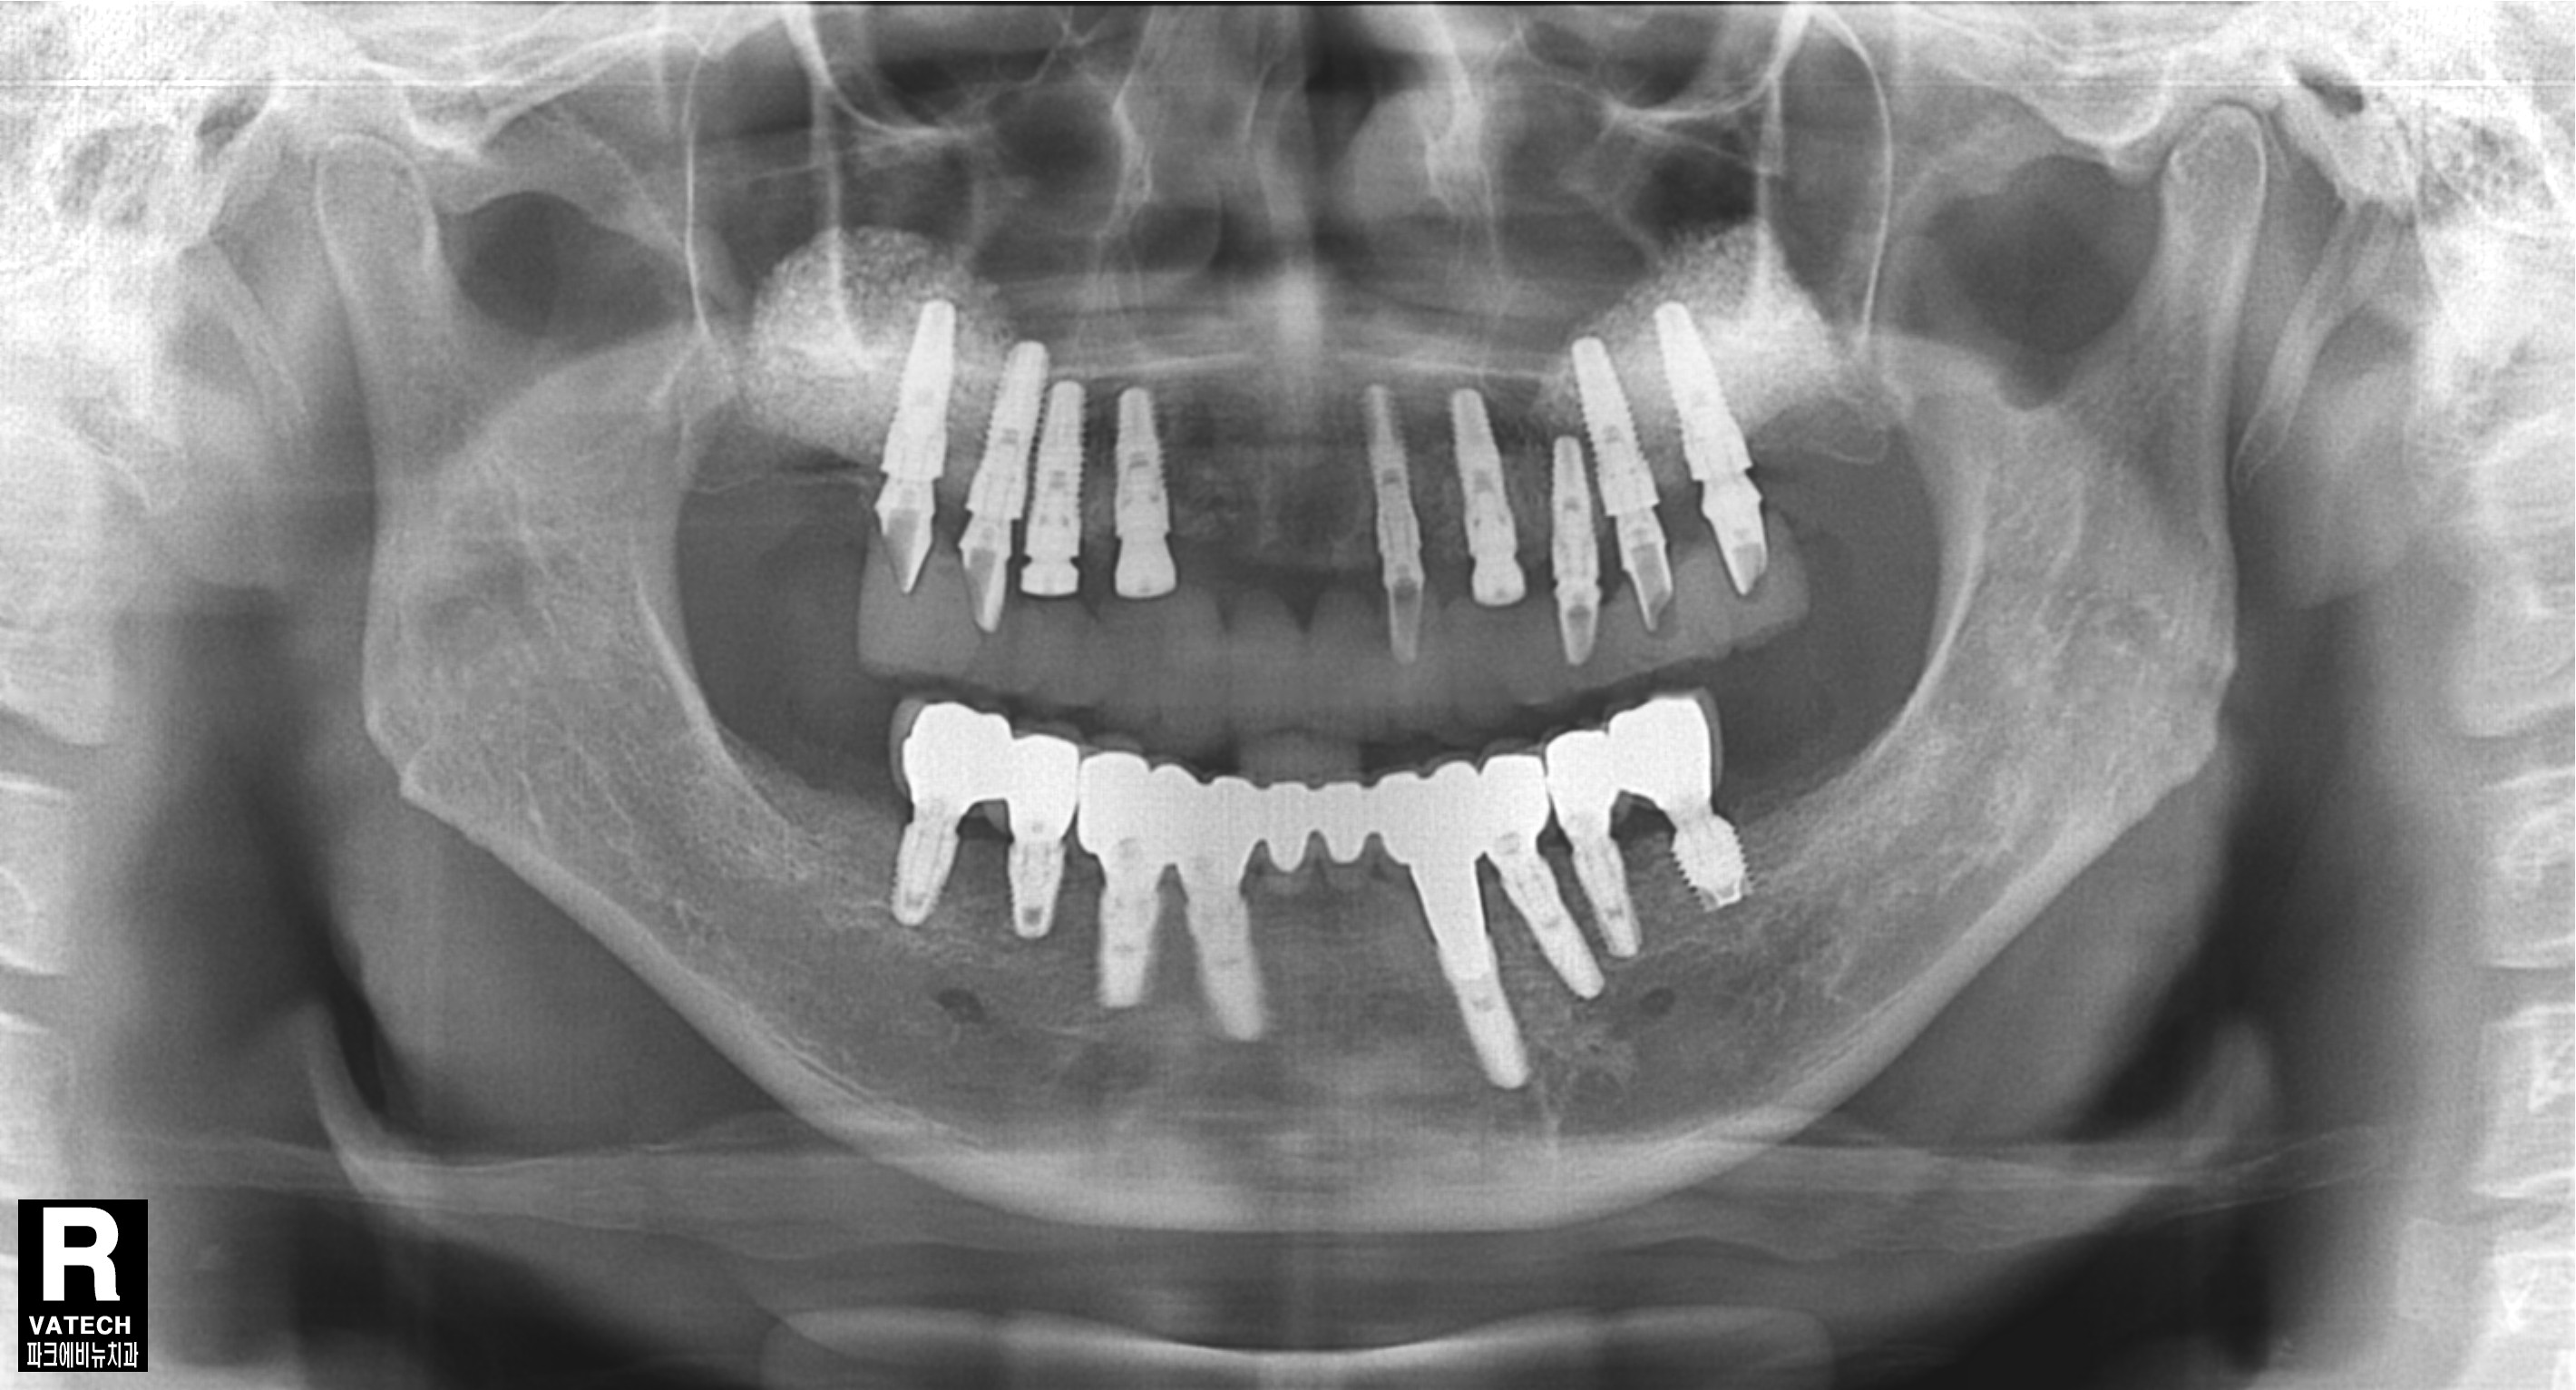

최종 보철물까지 올리고 난 후 구강 내 사진입니다.

평상시의 교합 뿐만아니라 좌우로 아래턱을 크게 움직였을 때도 불편함이 없습니다.

이후 환자분은 정기적으로 체크를 받고 계시고

이전에 좋지 않았던 구강위생도 계속적인 구강위생교육으로 많이 개선되었습니다.